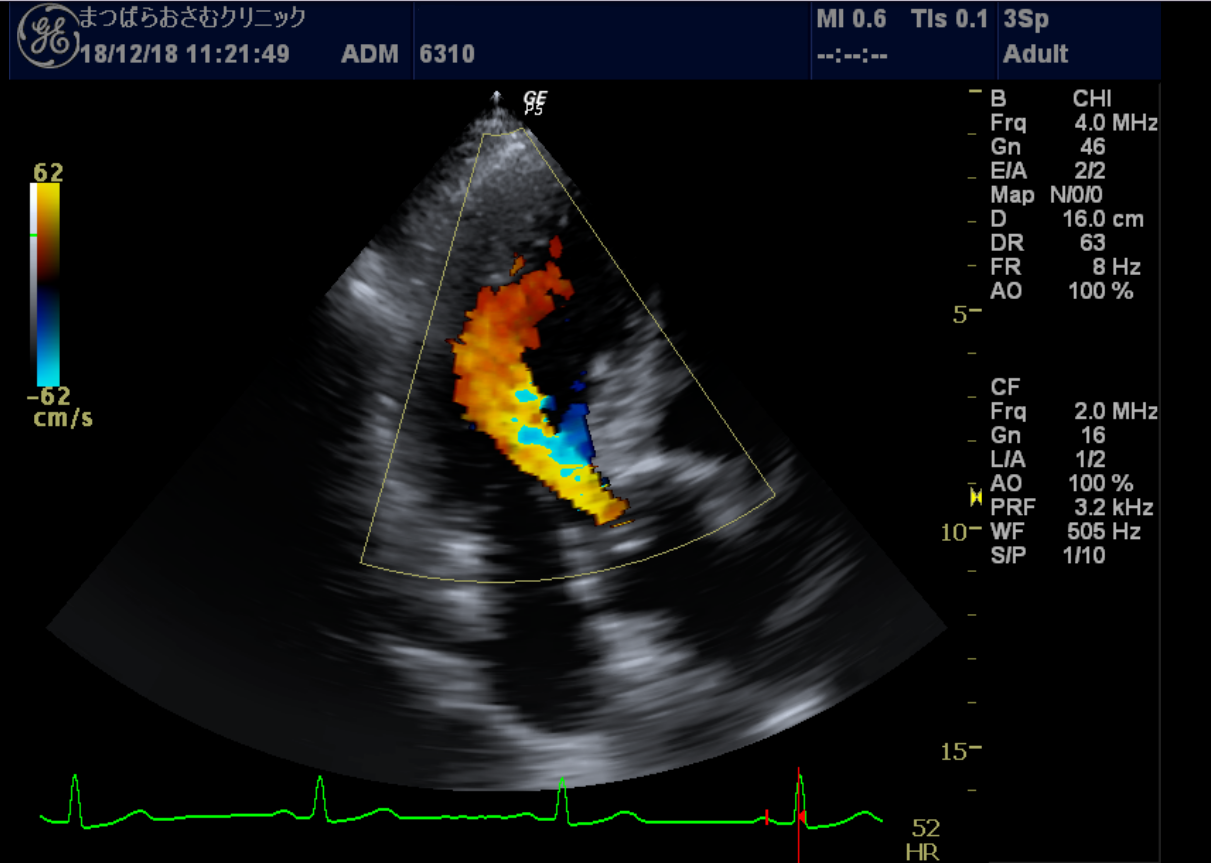

心エコー 心臓の動きや構造を観察する検査です。

胸にプローブ(探触子)を当てるだけで、心臓の大きさ、動き、弁の状態、血流の様子などをリアルタイムで確認できます。